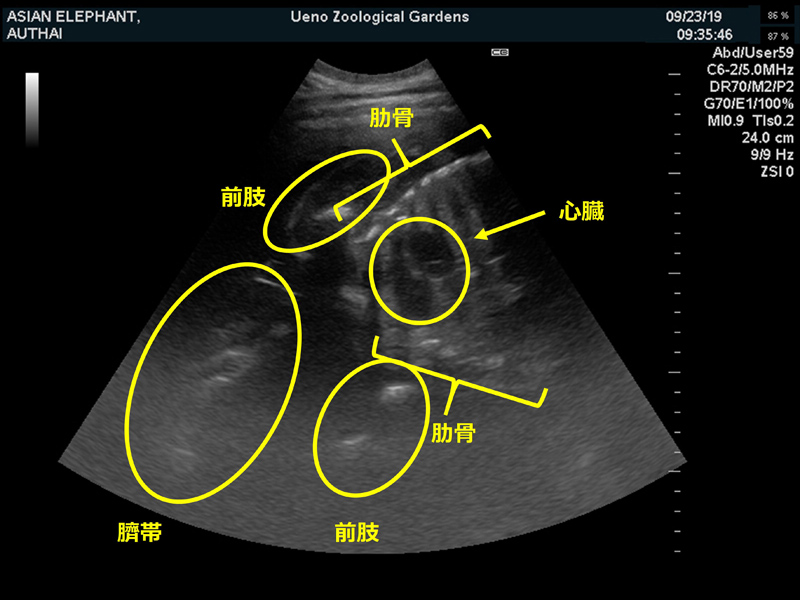

アジアゾウ「ウタイ」 (撮影日:2019年10月3日) | アジアゾウ「ウタイ」腹部超音波検査画像 (撮影日:2019年9月23日) |

2019年1月にウタイ(当時20歳)とアティ(当時22歳)を繁殖のため同居させたところ、1月13日及び14日にそれぞれ一度ずつ交尾が確認されました。その後、定期的に計測していたウタイの血中ホルモン(プロジェステロン)値が2月末ごろから上昇し、妊娠に至っていない場合には下がるはずの値が4月に入っても高いままであったこと、2019年9月23日に実施した超音波(エコー)検査により胎児の骨格と心拍が確認されたことから、妊娠と判断いたしました。